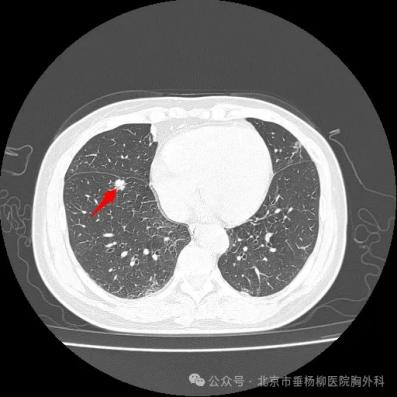

患者,女性,60岁,主因“发现右肺结节1年余”入院,胸部CT提示右肺上叶尖段磨玻璃结节,大小约2.1cm×1.2cm,边界欠清,无胸膜牵拉(图1),右肺下叶前基底段实性结节,大小约1.0cm×0.9cm,呈分叶状,边缘欠光滑,邻近胸膜牵拉(图2)。患者于我院行单孔胸腔镜下右肺上叶尖段、右肺下叶前基底段切除术及纵隔淋巴结清扫术。术后病理提示右肺下叶浸润性腺癌,贴壁型为主,未累及胸膜,右肺上叶微浸润性腺癌,未累及胸膜,第4组、7组、8组、9组、10组、12组淋巴结未见癌转移。患者术后2日拔出胸腔引流管,术后4日康复出院(图3)。

图1